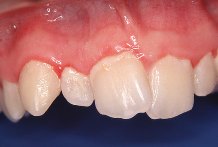

La causa m�s com�n es la placa bacteriana. Est�

formada por una capa pegajosa, casi invisible, que se acumula sobre la superficie de los

dientes cada d�a. La placa proviene de la saliva, de los restos de comida, del fluido que

sale del borde de la enc�a y de varios tipos de bacterias y sus productos. Con frecuencia

la placa bacteriana se endurece (calcifica) convirti�ndose en t�rtaro (lo que los

dentistas llaman c�lculo).

La placa es m�s abundante cerca de los bordes de

la enc�a y entre los dientes. En las personas que no mantienen una buena higiene bucal,

la mayor�a de las superficies dentales est�n cubiertas por una capa bacteriana. Casi

todos los adultos y ni�os tienen placa y c�lculo. La placa se compone en su mayor�a de

bacterias, sales minerales y agua. En el proceso de su formaci�n en capas, el c�lculo se

recubre sucesivamente con placa y con bacterias ocasionando la inflamaci�n de la enc�a

como consecuencia de la acci�n bacteriana y de las defensas del cuerpo para combatirla.